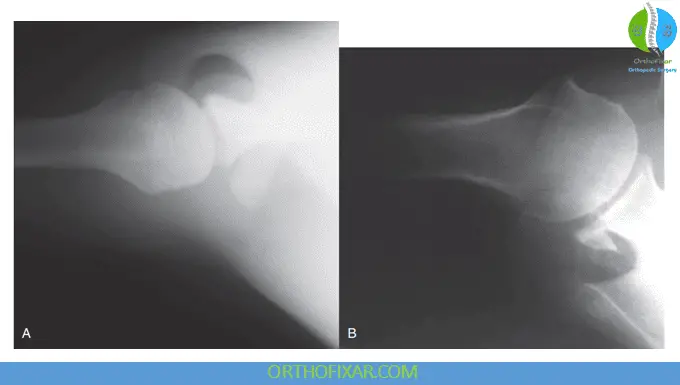

Hill-Sachs Lesion Identification: When the humerus is positioned in medial rotation during AP imaging, a defect may become visible on the lateral aspect of the humeral head. This defect, known as a Hill-Sachs lesion, represents a compression fracture of the postero-superolateral humeral head resulting from recurrent anterior dislocations. These lesions are classified as either engaged or nonengaged, with engaged lesions articulating with the glenoid during arm abduction and lateral rotation, potentially affecting joint stability.

Reverse Hill-Sachs Lesions: In cases of posterior dislocation, an anteromedial humeral head impression fracture may occur, known as a reverse Hill-Sachs lesion (RHSL), Malgaigne lesion, or McLaughlin lesion. These lesions occur in 30% to 90% of posterior dislocations and can be visualized on plain radiographs, CT scans, or MRI.